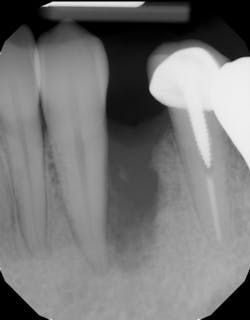

This surgical video demonstrates removal of a tooth with loss of buccal plate and grafting of the remaining socket with Geistlich Bio-Oss Collagen and Geistlich Bio-Gide to preserve the ridge for implant placement.

These alveolar bone changes often compromise implant placement due to thin bone volume (figures 2a–2d).

Unfortunately, many clinicians assume all grafting products are created equal and select the material based on price point alone. If the bone grafting material is not formulated correctly, degradation may not occur, and the graft can become fibrously encapsulated, leading to poor bone turnover and graft failure (figures 12a–12c).